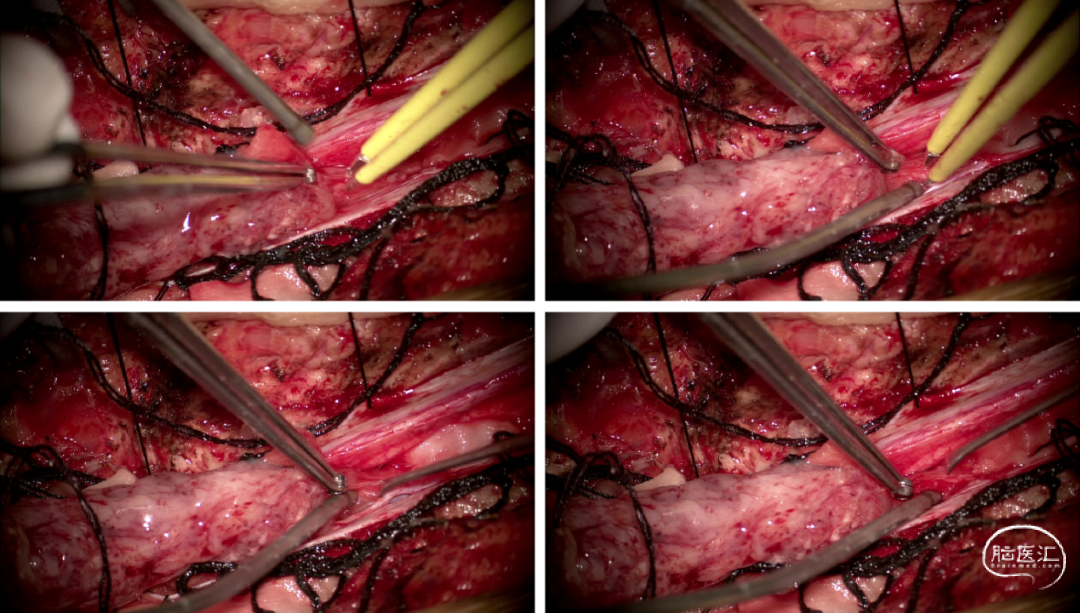

手术情况

硬脊膜张力高,脊髓向背侧膨出,与脊髓腹侧粘连紧密,肿瘤挤压脊髓,肿瘤边界分离,减少对胸髓的牵拉,降低了术后患者神经功能发生的概率,术后患者肢体麻木症状改善。